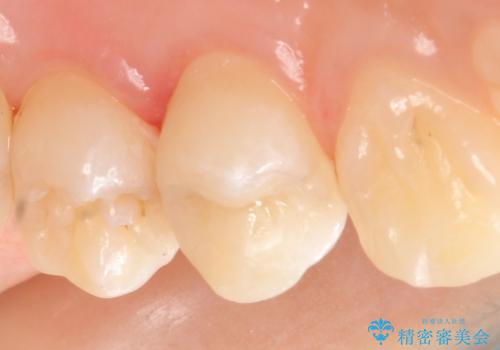

セラミックインレー 虫歯で欠けた歯の治療

- 左上4番目の歯が欠けてしまったので診て欲しいといらっしゃった方の症例です。

白い詰め物を御希望されたので、セラミックインレーによる修復を行いました。

当院のセラミックインレーはemaxという強度と審美性に優れた材料を使用しています。

またプレス方式でインレーを製作しているため、削り出しで製作するCADCAMより優れた適合性も持ち合わせており、虫歯が再発しにくい修復物です。